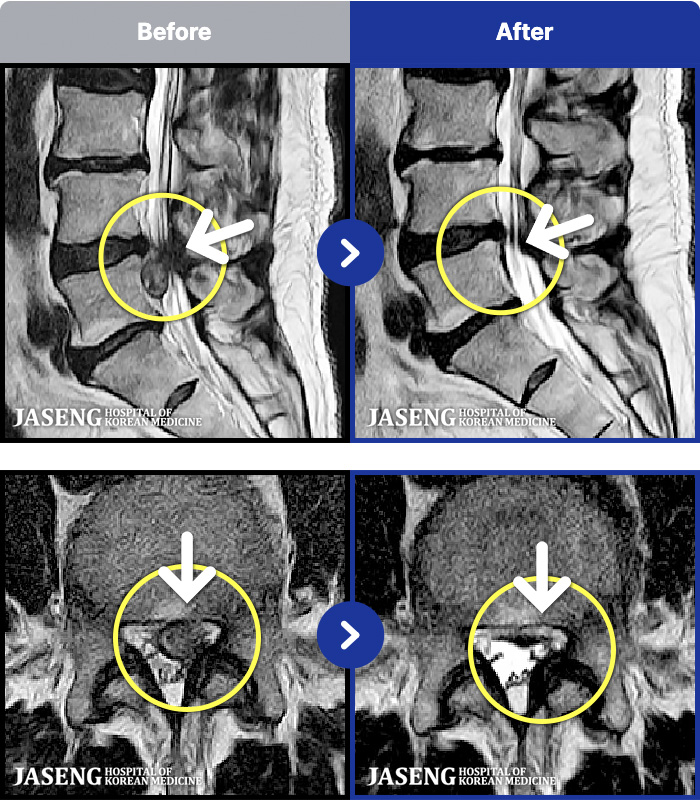

- MRI ġ

MRI ġ

MRI ũ ʸ Ȯϼ.